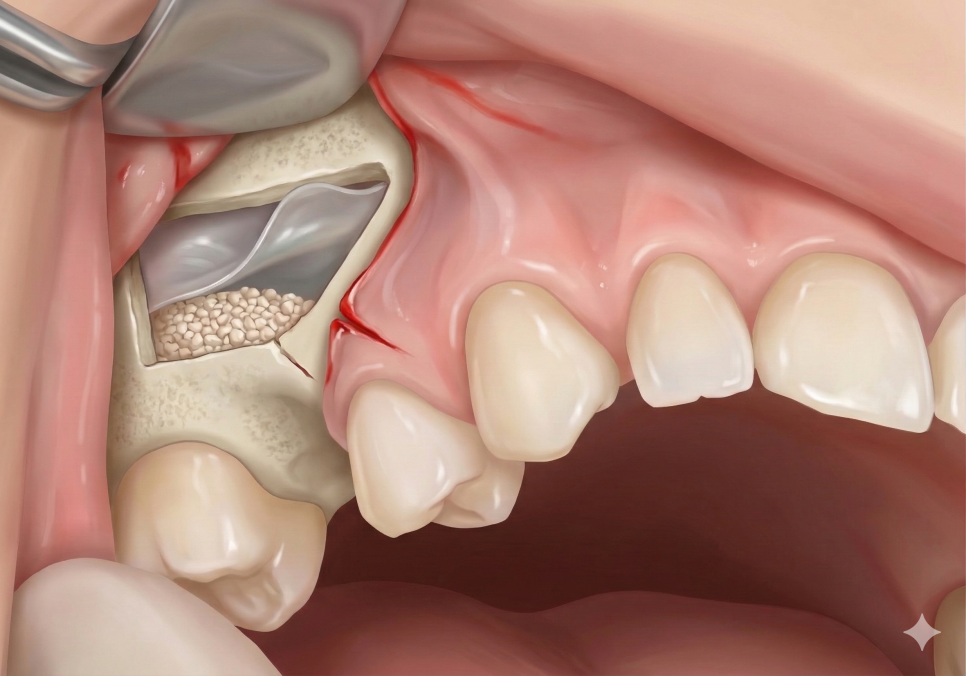

이번 사례처럼 뼈가 아주 매우 얇은 경우에

선택하는 방법이에요.

상악동 뼈의 옆면을 통해 접근하여

막을 들어 올리고 뼈를 이식하게 됩니다.

직접 시야를 확보해야 하고,

얇은 상악동 막이 찢어지지 않도록

아주 정교하게 다루어야 하는

고난도 술식으로 꼽히죠.

환자분은 뼈가 1.1mm로 워낙 얇았기 때문에

임플란트를 고정할 최소한의 힘조차

얻기가 어려웠습니다.

그래서 저희는 옆면으로 안전하게 접근하는

측방 거상술을 통해

충분한 양의 뼈를 이식하고

임플란트를 식립하기로 결정했습니다.

240329

고난도 수술이었지만

다행히 상악동 막이 아주 예쁘게 잘 올라갔고

뼈 이식도 안정적으로 이루어졌네요.^^